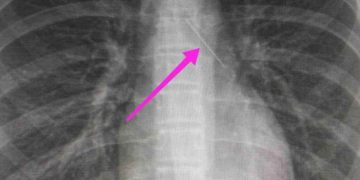

Από την απεικονιστική διερεύνηση που πραγματοποιήθηκε με ακτινογραφία θώρακος αρχικά και ακολούθως με αξονική τομογραφία θώρακος, διαπιστώθηκε «η ύπαρξη αιχμηρού μεταλλικού ξένου σώματος στην αναπνευστική οδό (αριστερός κύριος βρόγχος) και όχι στην πεπτική οδό».

Κατά την βρογχοσκόπηση διαπιστώθηκε η μετακίνηση και ενσφήνωση του ξένου σώματος στον δεξιό κύριο βρόγχο. Μετά από εργώδεις προσπάθειες ολοκληρώθηκε με επιτυχία η αφαίρεση του.